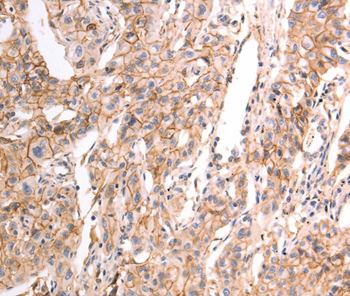

Immunohistochemical analysis of paraffin-embedded Human breast cancer tissue using #37301 at dilution 1/30.

Immunohistochemical analysis of paraffin-embedded Human liver cancer tissue using #37301 at dilution 1/30.